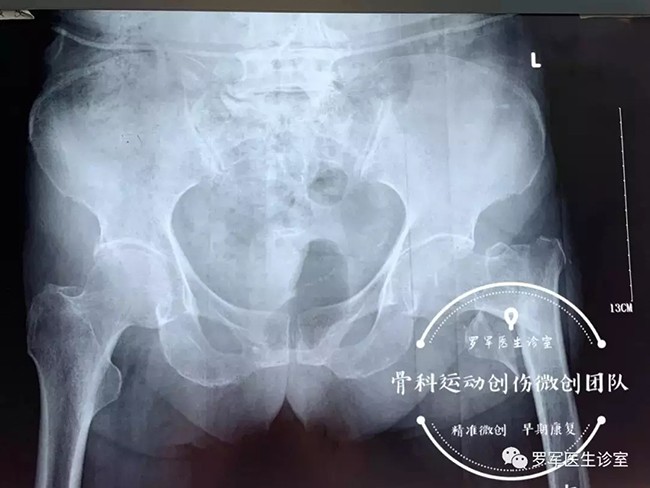

今年86歲高齡的丁奶奶就是其中的一位患者,前不久,丁奶奶走路時(shí)不幸摔倒,造成左側(cè)股骨粗隆間粉碎性骨折,被送到廣安醫(yī)院關(guān)節(jié)科救治。

經(jīng)過入院檢查發(fā)現(xiàn)丁奶奶合并有高血壓,糖尿病,動(dòng)脈粥樣硬化、低蛋白血癥及嚴(yán)重的骨質(zhì)疏松,“無論采取保守治療還是手術(shù)治療,風(fēng)險(xiǎn)都很大。但對(duì)于高齡老人的骨折,放棄手術(shù)就等于放棄生的希望。”羅軍主任介紹,髖部骨折對(duì)高齡、身患各種慢性病的老年人來說無疑是大難題,而且由于骨折后老人臥床至少需要三個(gè)月以上,由此引發(fā)的并發(fā)癥,如褥瘡,肺炎、血栓、泌尿系感染等都很容易導(dǎo)致老人死亡。因此,髖部的骨折被稱為老年人“人生的最后一次骨折”。

5月7日,羅軍主任帶領(lǐng)手術(shù)團(tuán)隊(duì)按照術(shù)前的討論方案,在C臂機(jī)透視下,采用三個(gè)微創(chuàng)手術(shù)通道,施行精準(zhǔn)閉合復(fù)位、定位、固定,僅用了大約30分鐘,便成功完成微創(chuàng)內(nèi)固定手術(shù)。手術(shù)進(jìn)行順利,第二天老人就可以在床邊坐起了。老奶奶非常開心,叫家人一定要送面錦旗給醫(yī)生。